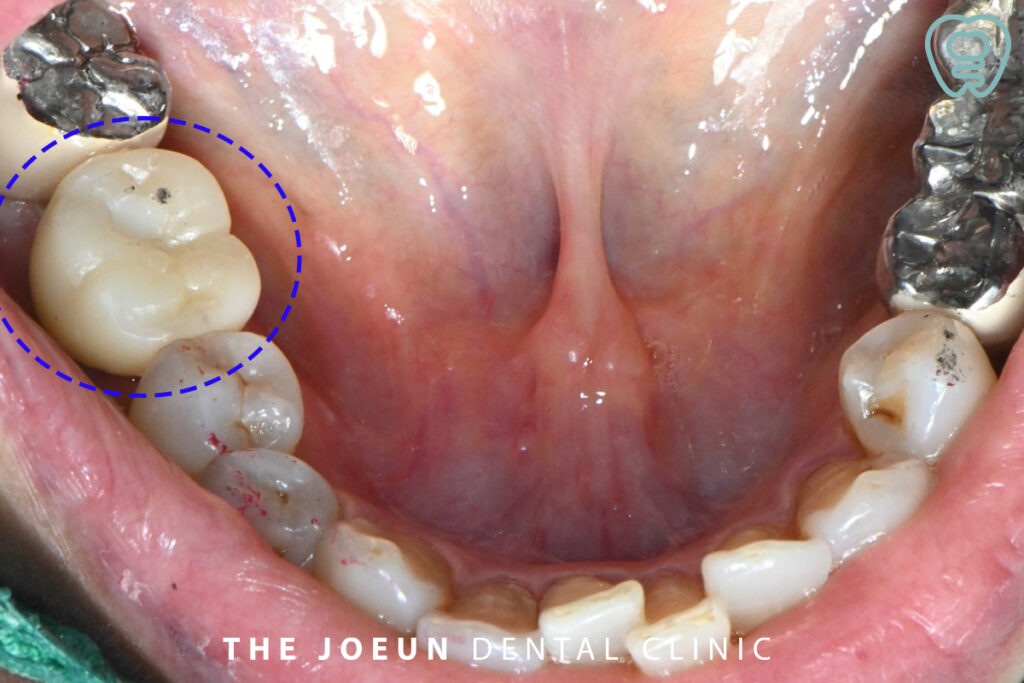

환.자분께서는 오른쪽 아래 씌운 치아가 식사하실 때 통증이 느껴지신다며 불편함을 호소하셨는데요. 이미 신경치료를 마친 후, 전체를 씌워놓은 상태로 자연치아의 보존을 위해 먼저 재신경치료를 진행해 보기로 하셨습니다.

기존의 치아 상태를 면밀하게 살펴본 후 크라운을 제거하고 신경관을 메우고 있는 충전재를 제거하여 재신경치료를 진행하였는데요.

이미 신경치료가 되어 있는 치아를 재신경치료 하는 것은 처음보다 난이도가 높고 조건도 까다로우며 고려해야 할 사항이 많아 성공률도 낮고, 환.자분의 경우와 같이 치아에 금이 가 있다면 예후가 좋지 않아 자칫 발치가 필요할 수 있는 상황임을 설명드린 후 치료를 진행했으나 치아의 원심 부분에 깊이 금이 간 것을 발견하였고 계속적으로 증.상이 호전되지 않아 발치 후 즉시 임플란트를 진행하기로 하였습니다.